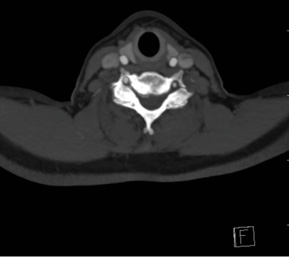

This patient is a 58 year-old female radiology technician with chronic, intractable neck pain, right > left arm radicular pain, and progressive weakness. At one point her symptoms worsened so acutely, she presented to the emergency department for acute triage with cervical CT angiogram, which showed advanced spondylosis at the C6/7 level.

The combination of the chronic problem with acute worsening of symptoms required decompression and stabilization at C6/7. Typically, at this patient age, with this advanced level of spondylosis at the C6/7 level, I would proceed with an instrumented fusion. However, this patient was very active and wanted to optimize her quality of life as possible with this surgery.